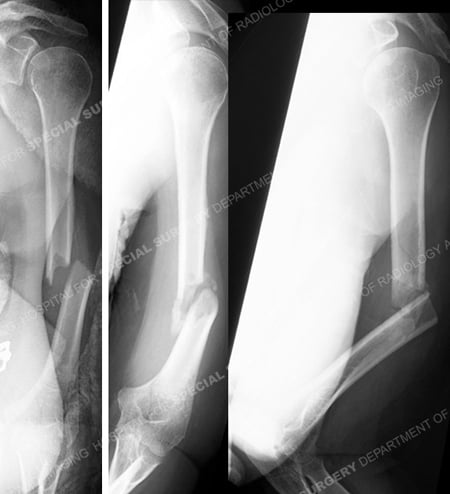

Anteroposterior injury radiograph (left image) revealing a mid-shaft humerus fracture with a fracture line extending to the distal humerus and radiographs at 6 months following the injury (right images) illustrating a humeral nonunion with significant deformity.